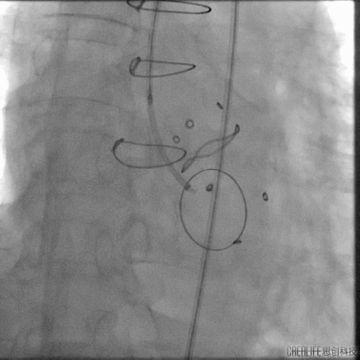

瓣上造影

造影可见主漏及无窦附近明显瓣周漏;

建立瓣周漏轨道

血管塞封堵

12mm三支血管塞置入

术中食道超声确认满意后释放血管塞